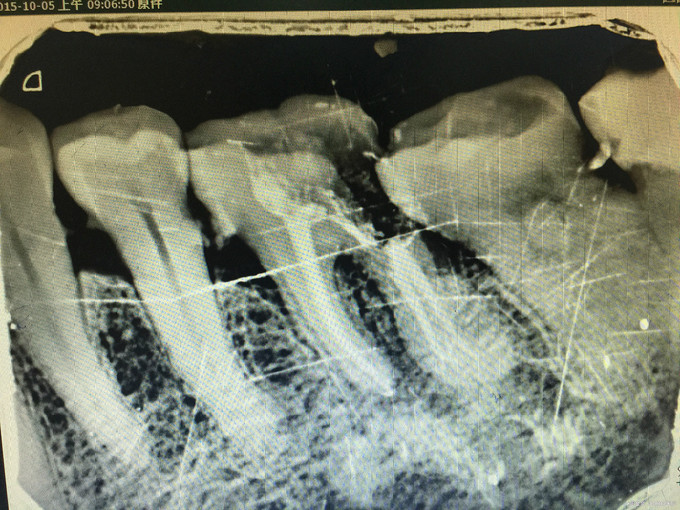

临床检查:36远中邻面龋坏,探疼(+),冷(++),叩(-)可探及穿髓点,无窦道,松动度(-),牙周正常. 辅助检查:X线示36远中龋坏累积髓腔。

诊断:36牙髓炎 治疗:经患者知情同意后,36局麻去腐降牙合,开髓拔髓寻找根管口,建立直线通路,扩通根管,确定工作长度。vdw/EDTA凝胶镍钛器械,低浓度次氯酸钠冲洗根管,预备至25/06,氢氧化钙诊间封药,一周后复诊,试主尖X线示恰充,试干根管,导AH-PLUS糊剂,VDW热压胶垂直加压根充,术后见根管恰充,暂封嵌体修复。